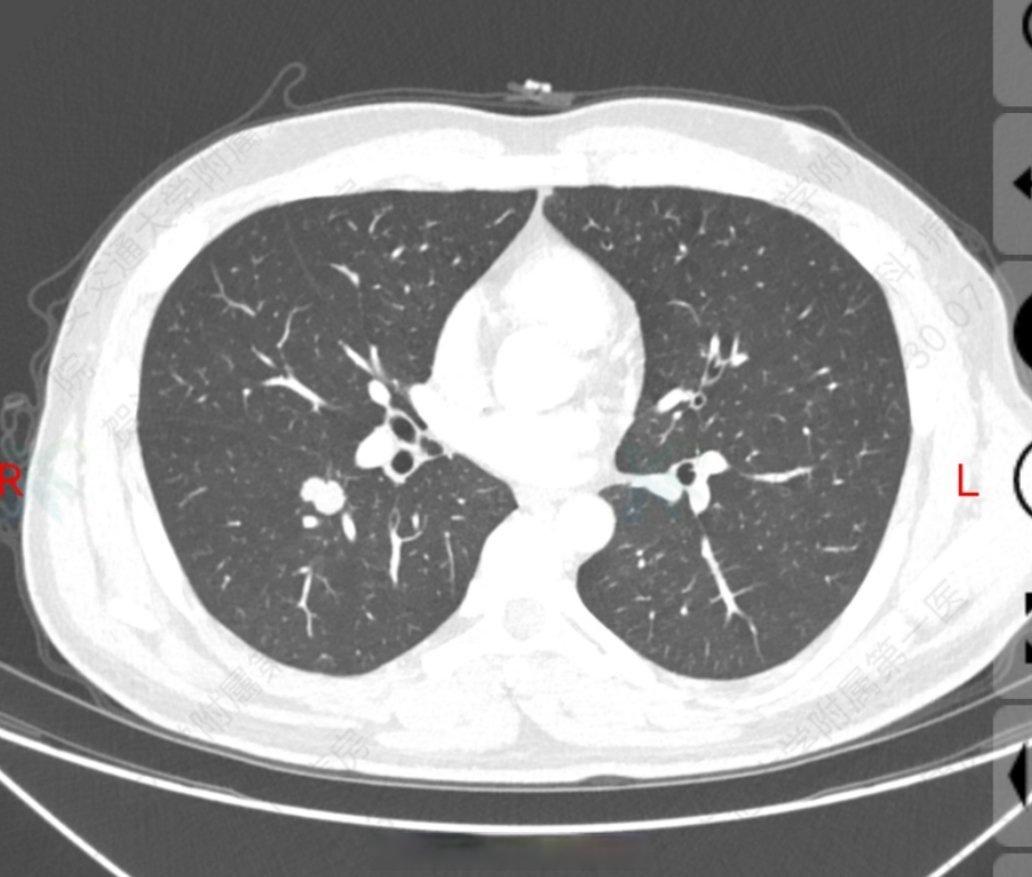

CT显示右肺下叶微小结节指在胸部CT检查中发现右肺下叶存在直径小于1厘米的结节性病变,其性质可能为良性或恶性,需通过进一步检查明确一结节的可能病因良性病因包括感染因素如细菌病毒非结核分枝杆菌感染良性肿瘤如腺瘤错构瘤恶性病因则可能为原发性肺癌如腺癌鳞状细胞癌或转移;非感染性因素肺部良性肿瘤如错构瘤,与胚胎发育异常相关,生长缓慢肺部恶性肿瘤周围型肺癌早期可能表现为结节,恶性结节在右肺上叶区域的发生率需重视肺部炎性假瘤由慢性炎症刺激导致,表现为局限性增生性病变职业性肺疾病长期接触粉尘如煤尘石棉可能导致尘肺,影像学上表现为结节三。

右肺结节是在进行胸部影像学检查如X线CT等时发现的肺部圆形类圆形或不规则形状的阴影,直径小于或等于3厘米其中,直径小于1厘米的称为小结节,直径小于05厘米的称为微小结节肺部结节的性质具有不确定性,可能是良性的,也可能是恶性的发现右肺结节后,需及时就医,医生会依据结节的大小;右肺中叶结节是指在胸部影像学检查如胸部CT中,发现右肺中叶存在类圆形或不规则形直径通常小于3厘米的密度增高阴影常见原因感染性因素包括细菌如肺炎链球菌病毒如腺病毒及结核分枝杆菌感染细菌感染引发肺部炎症后,修复过程中可能形成结节病毒感染导致肺组织炎性损伤,修复时也可能形成结节样组织结核。